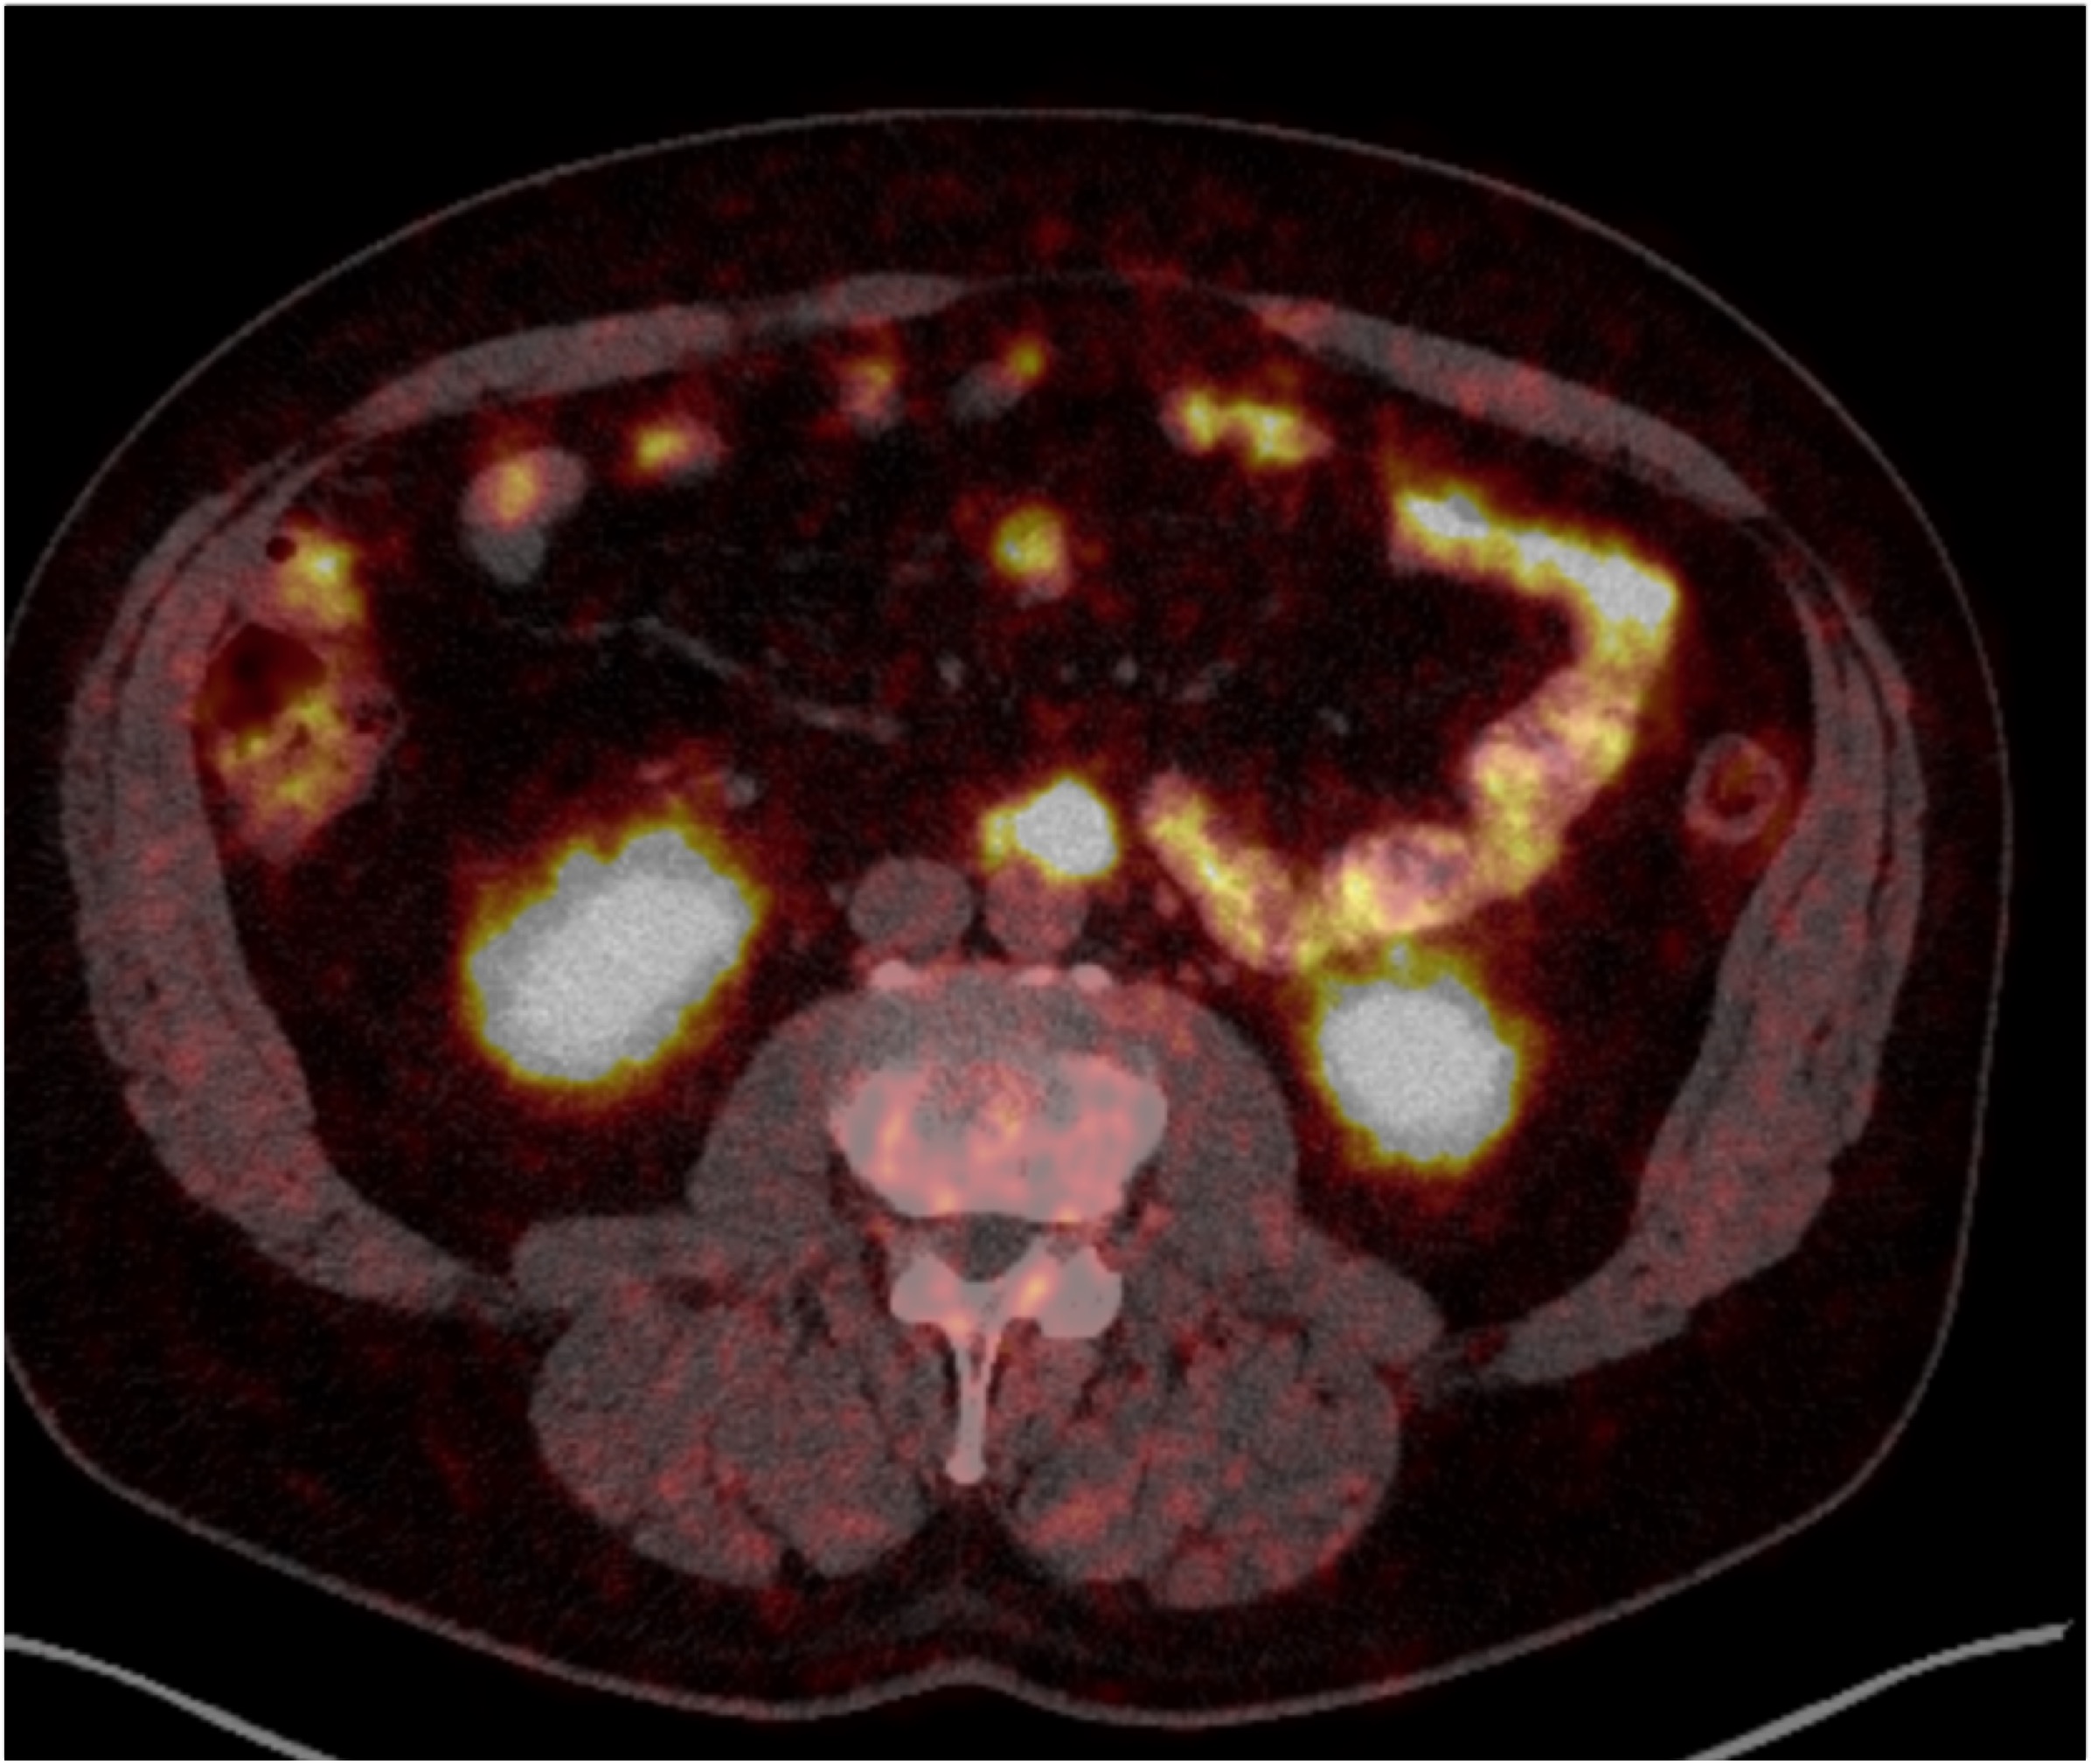

8) The most likely diagnosis for the dominant left renal mass is?

clear cell renal cell carcinoma

metastatic melanoma

papillary renal cell carcinoma

renal oncocytoma